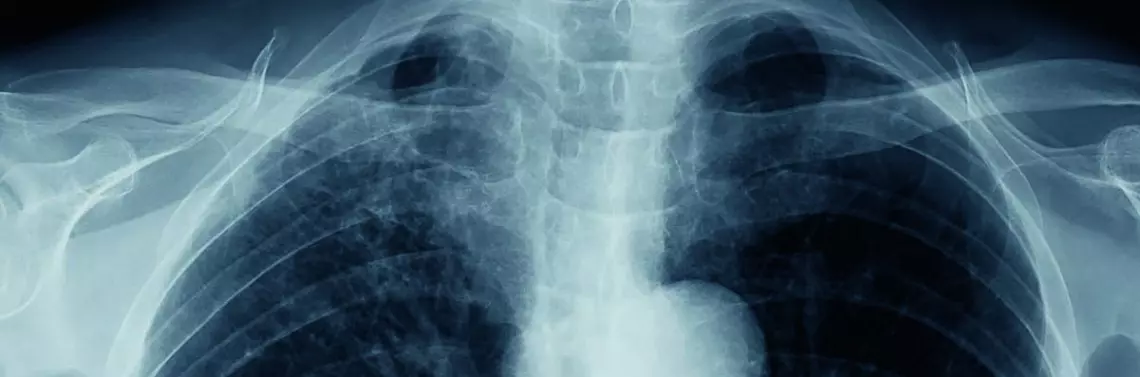

Zapalenie suche opłucnej jest pierwszą fazą wysiękowego zapalenia opłucnej (zdj. 1). Pacjent odczuwa bardzo silny, kłujący ból w klatce piersiowej, który nasila się podczas poruszania lub głębokiego oddechu. U chorego występują poty i gorączka. Ból jest spowodowany ocieraniem się o siebie blaszek opłucnej ściennej i opłucnej płucnej. Blaszki opłucnej są obrzęknięte, przekrwione, a na ich powierzchni odkładają się złogi włóknika. Gromadzenie się płynu prowadzi do oddalenia się od siebie blaszek opłucnej, co powoduje złagodzenie dolegliwości bólowych u pacjenta. Zwiększająca się ilość płynu doprowadza do uciśnięcia płuca i odsunięcia go od ściany klatki piersiowej (zdj. 2). Powoduje to pojawienie się w płucu niedodmy oraz zmniejszenia w nim powietrzności, co skutkuje pojawieniem się u chorego duszności. Duży wysięk powoduje odczuwanie przez pacjenta tępego ucisku w klatce piersiowej [1, 2].